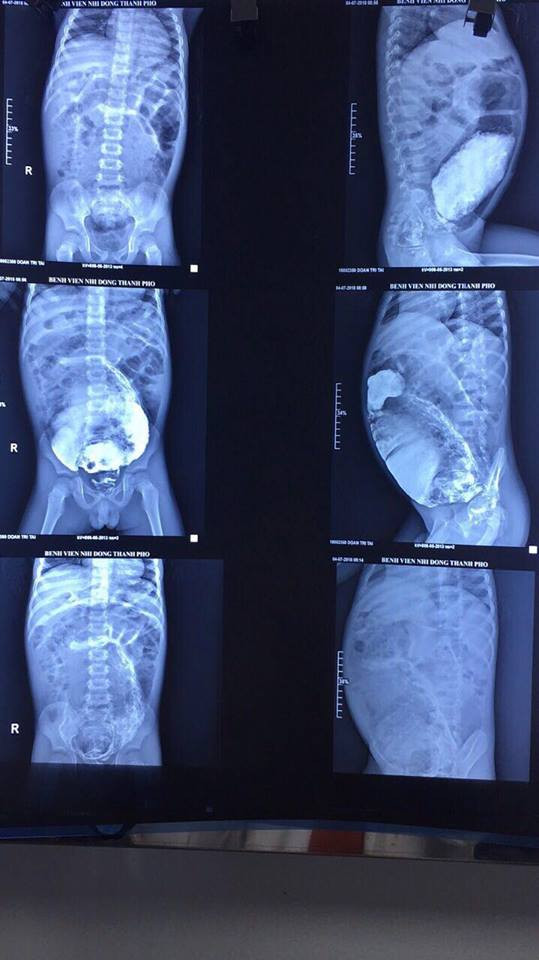

Ảnh chụp phim cho thấy đại tràng bé giãn to, ứ đầy phân.

Qua thăm khám và chụp phim, các bác sĩ chẩn đoán bé bị hội chứng phình đại tràng bẩm sinh, khiến một đoạn đại tràng không có dây thần kinh để kiểm soát sự co bóp.

Ekip điều trị dưới sự hướng dẫn và tham vấn từ PGS.TS Trương Nguyễn Uy Linh, người gắn bó với hàng trăm ca mổ phình đại tràng bẩm sinh đã thực hiện ca phẫu thuật cho bệnh nhi. Ca mổ kéo dài 3 giờ để cắt bỏ phần trực tràng bị phình dài gần 20 cm, giãn to 20 cm cùng gần 3 kg phân ứ đọng bên trong.